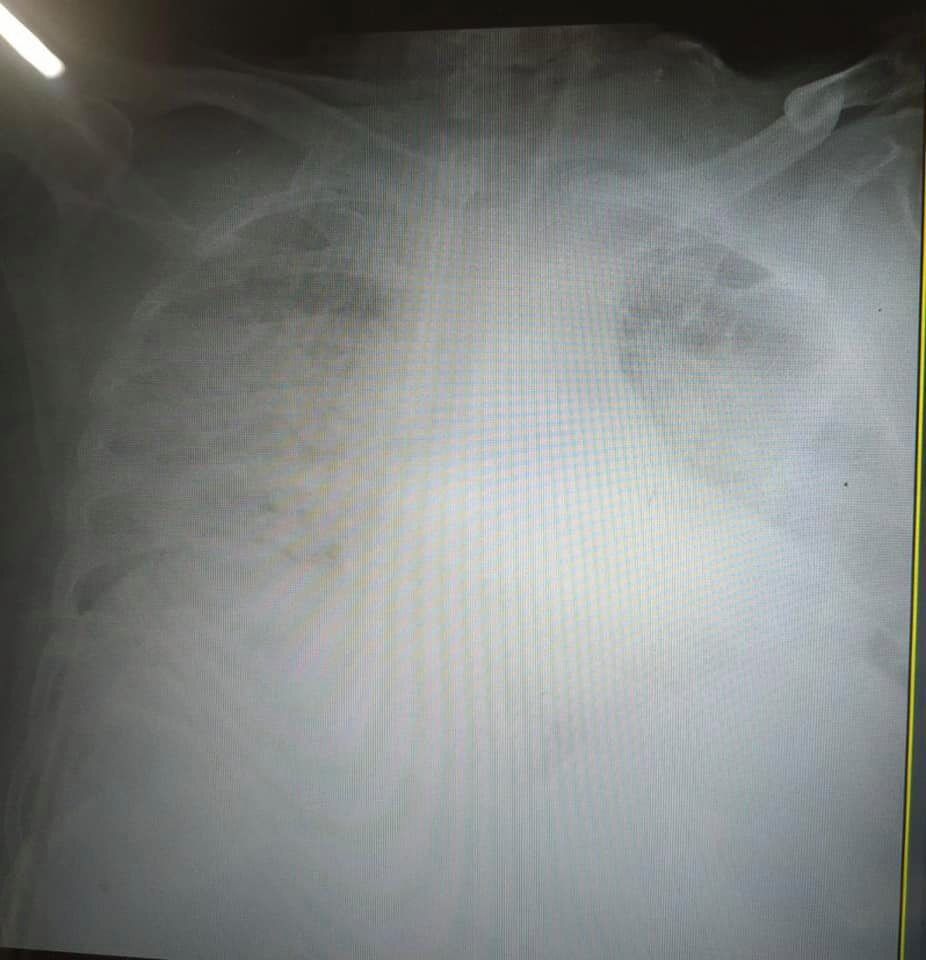

Украинская журналистка Ирина Заславец показала фото рентгена легких, пораженных коронавирусной болезнью (COVID-19).

Снимки она опубликовала в Facebook после общения с главой реанимации Клинической больницы скорой медицинской помощи Львова Натальей Матолинец.

"Это одни из самых страшных легких, которые я видела в жизни", – отметила врач.